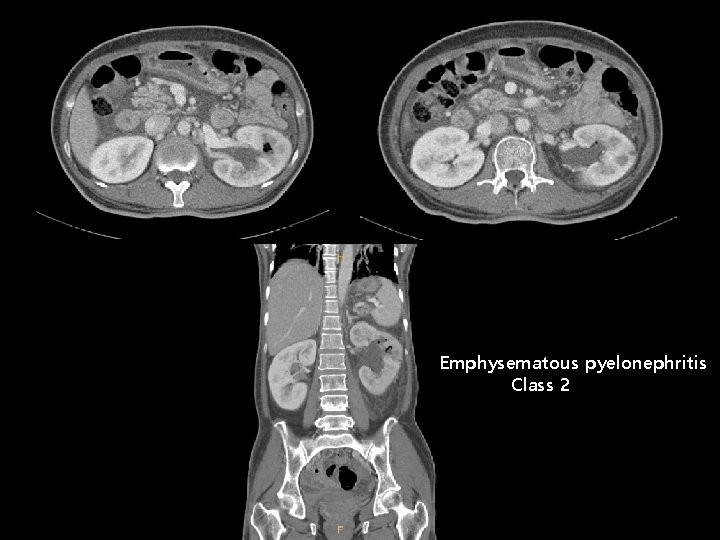

이 O 선 (F/50) • C/C : Fever, chill, Lt. flank pain • DM (2000’) : No medication, Hb. A 1 c 15. 9 % • CBC 5, 500 (Neut. 94. 7%) – 13/38. 1 -211 K, CRP 13. 54 Glucose 623 BUN/Cr 11/0. 65 (e. GFR 102. 5) Na/K/Cl/TCO 2 130 – 4. 0 – 87 - 28 RUA glucose 2+, protein 1+, blood 2+, leukocyte 1+ RBC 5 -9/HPF, WBC 10 -29/HPF

Emphysematous pyelonephritis Class 2

• • Tabaxin inj. 4. 5 g [Tazobactam/Piperacillin sodium] q 8 hr IV PCD insertion